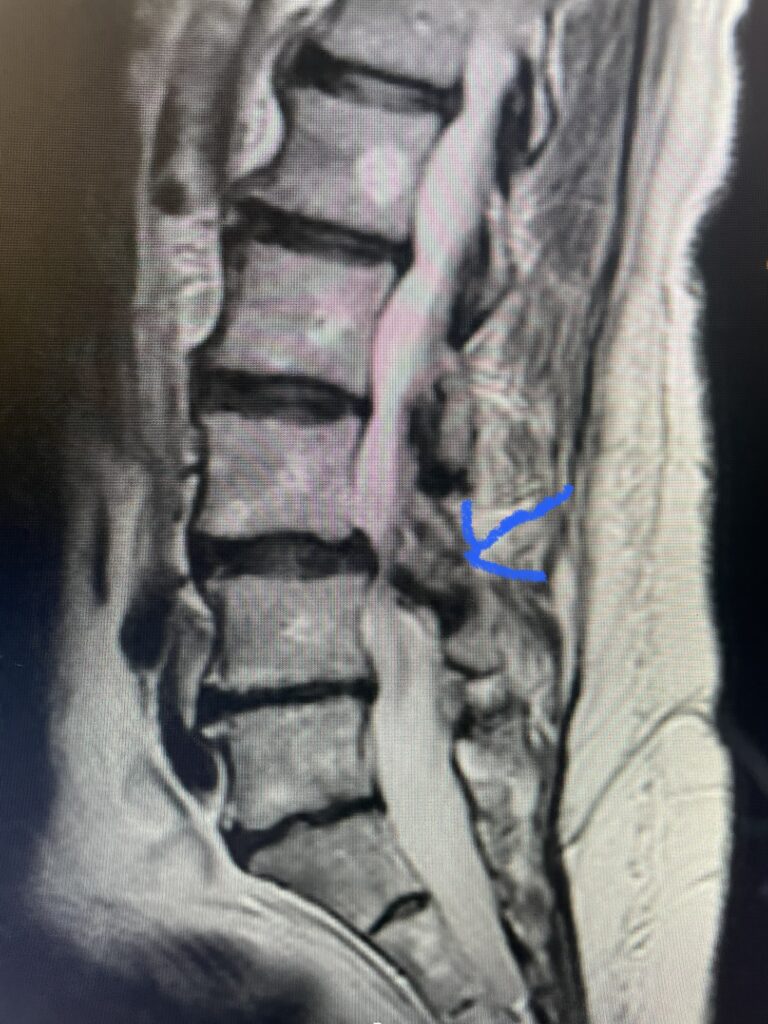

The actual structural cause of lumbar thecal sac compression can vary in degenerative spondylolisthesis and stenosis. The culprits are commonly thickened ligamentum flavum or severe facet […]

After 25 years in practice, I still find it challenging, but quite rewarding: removing degenerative material off the dural membrane in the lumbar spine. Some people […]